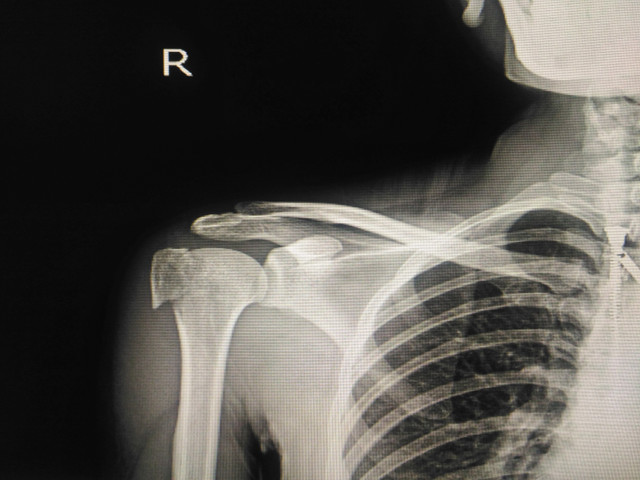

비교적 간단하게 상담과 진찰, 운동범위 측정등과 X-Ray나 관절초음파 등으로 확진할 수 있습니다.